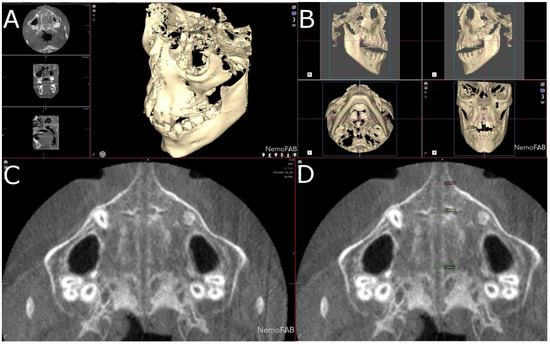

Figure 3.

(A) Boundaries of the palatine suture (blue line) after the RME procedure through McNamara appliance was performed, at transversal plane, (B) sagittal plane, (C) coronal plane and (D) at three-dimensional reconstruction of the CBCT scan.

Afterwards, a reference point (seed point) was placed inside the selected and isolated geometric prism of the expanded palatine suture at the transversal (Figure 4A), sagittal (Figure 4B) and coronal (Figure 4C) plane and the three-dimensional reconstruction (Figure 4D). This was to ensure a tissue density with a tolerance range of 500 Hounsfield units (HU), corresponding to the soft tissue density formed after the palatine suture expansion was performed according to the study of Buzatu et al. who measured the density of the palatal suture after RME procedures ranging between 128.56 HU (middle segment in women) and 398.07 HU (posterior segment in men) [27]. In the present study, a 500 HU tolerance range was established to ensure that the entire palatal suture expansion was registered inside the previously defined geometric prism.

Figure 4.

(A) Boundaries of the palatine suture (blue line) after the RME procedure through McNamara appliance with the seed point inside, at transversal plane, (B) sagittal plane, (C) coronal plane and (D) at three-dimensional reconstruction.